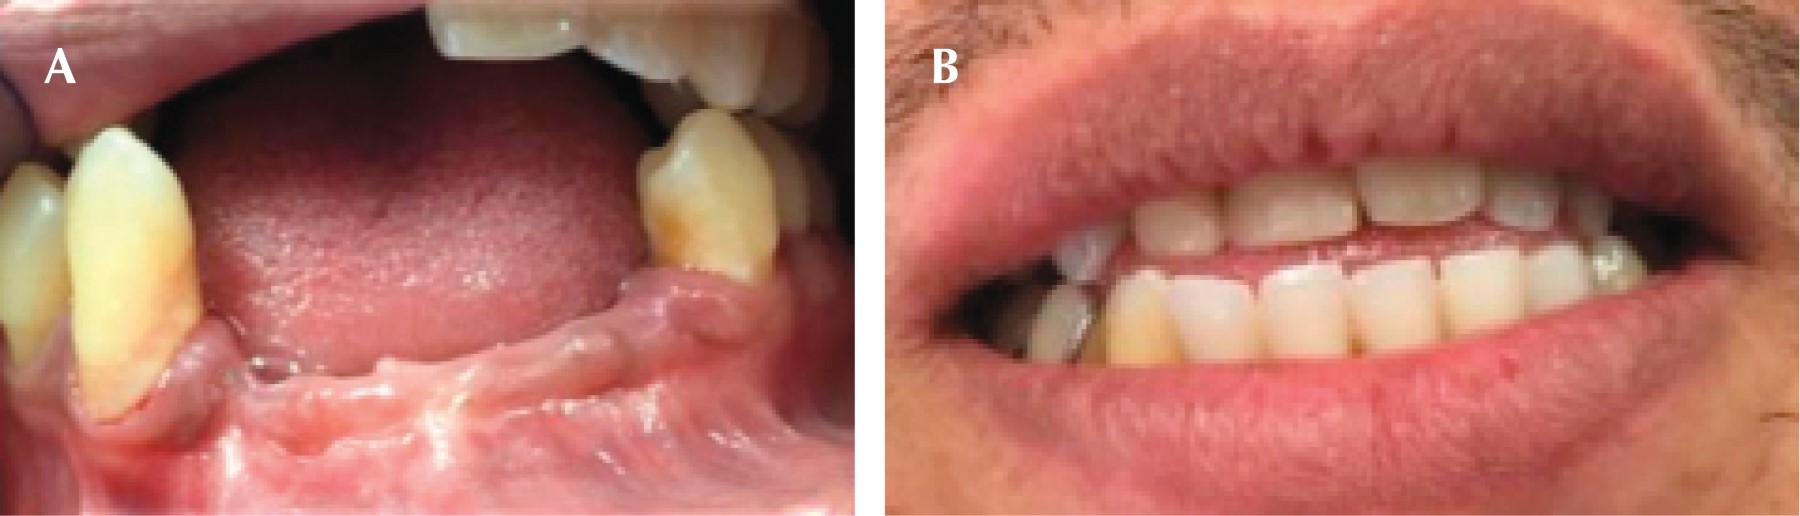

Seis años después acude nuevamente, presentando las siguientes características: agrandamientos gingivales de tipo inflamatorio generalizados, presencia de biofilm microbiano, cálculo supragingival y subgingival, abscesos periodontales, recesiones gingivales, todo esto evidencia un desapego al mantenimiento periodontal. Los niveles de glucemia obtenidos por medio de la toma capilar fueron de 450 mg/dL (Figura 4A-C).

Se inició la fase I y con base en la adherencia al tratamiento periodontal y un adecuado seguimiento, a pesar de la renuencia de iniciar un tratamiento sistémico se obtuvo una respuesta favorable. El paciente abandona el tratamiento por dos años, a su regreso afirmó que ya es diabético e hipertenso, sometido a tratamiento a través de metformina y enalapril respectivamente. Por medio de radiografías panorámicas y la inspección clínica se observó mayor pérdida ósea generalizada, lo cual mostró la progresión de la enfermedad periodontal, debido al desapego al tratamiento y la suma del factor sistémico (Figura 7A y B). Se inició (nuevamente) la fase I periodontal, realizando múltiples extracciones, debido a las condiciones en las que se presentó. Posteriormente se rehabilitó por medio de una prótesis parcial removible provisional inmediata (Figura 8A y B).